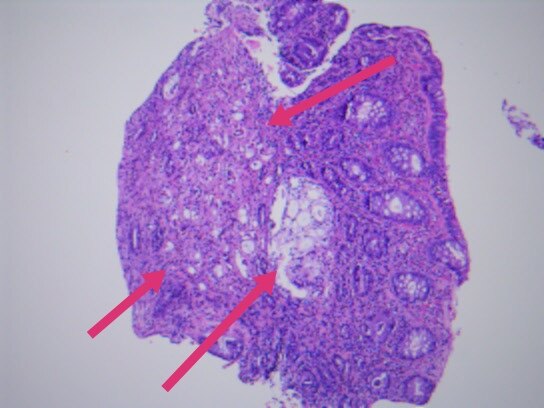

几天前,入我院行肠镜检查,并活检,显微镜下可见癌浸润于直肠粘膜之间。

最终,我们以上述HE形态为线索,老年男性,直肠占位,为XY坐标,我们初步音箱诊断就是前列腺腺泡腺癌浸润至前列腺腺外,累及直肠并形成肿块,浸润直肠全层至粘膜内。

上述免疫组化结果辅助诊断为前列腺腺泡腺癌累及直肠。